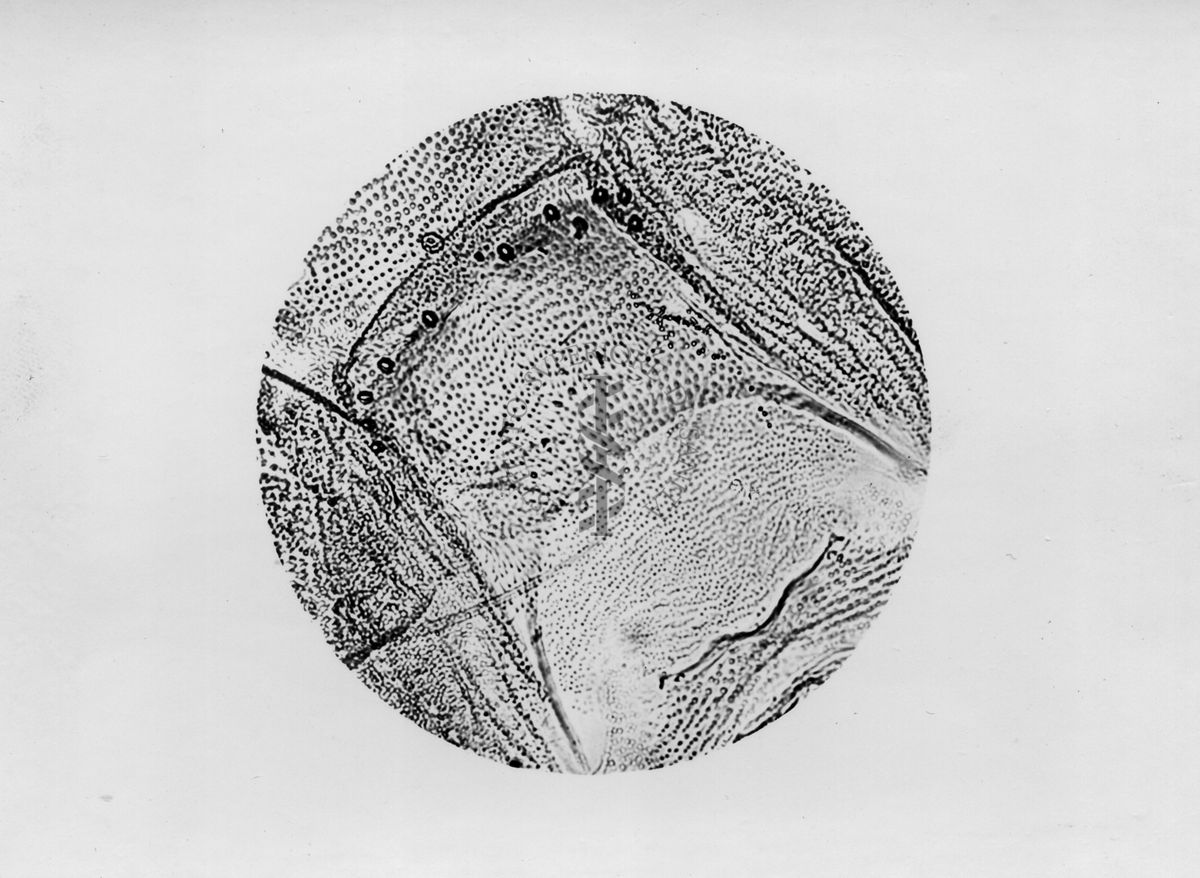

Microfotografie illustranti differenze morfologiche tra le specie P. Perniciosus e P. Perfiliewi

Microfotografia illustrante differenze morfologiche tra le specie P. Perniciosus e P. Perfiliewi